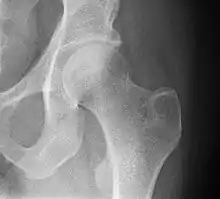

La surface articulaire fémorale de l'articulation coxale est constituée de la tête fémorale. Elle forme les deux-tiers d'une sphère de 20 à 25 mm de rayon Elle est entièrement recouverte de cartilage à l'exception de la fossette de la tête du fémur.

La tête fémorale s’insère dans la cavité cotyloïde concave située sur la face latérale de l'os coxal. La cavité est formée par l'acétabulum qui n'est recouvert de cartilage que sur sa partie périphérique sous la forme d'un croissant formant la surface lunaire de l'acétabulum. La partie profonde non articulaire n'entre pas en contact avec la tête fémorale et en est séparé par un paquet adipeux.

La cavité est approfondie par le labrum acétabulaire, structure en fibrocartilage entourant totalement la cavité cotyloïde.

En bleu, le croissant encroûté de cartilage.